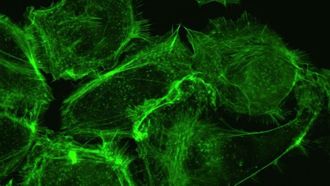

- يعد معهد العلوم البيولوجية في دبي رائداً في تطوير بروتوكولات متقدمة للكشف...

- طور باحثون في معهد كارولينسكا بالسويد روبوتات نانوية قادرة على قتل الخلاي...